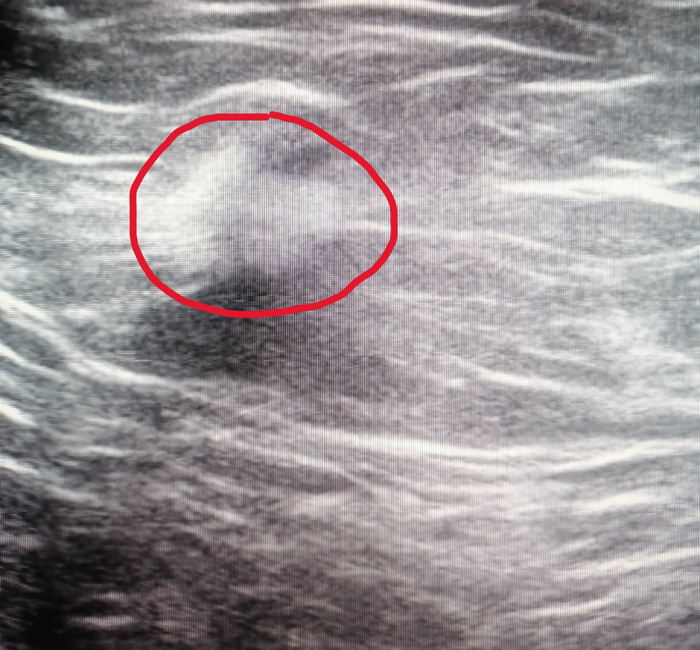

🔍 Улика №4 (ключевая): Там была история наблюдения за образованием в лёгком: 2 года назад — 2 см, год назад — 3.5 см с признаками роста, сейчас — уже есть метастазы в лимфоузлах.

Разгадка: У бабушки был карциноидный синдром — состояние, при котором некоторые опухоли (в данном случае в лёгком) выделяют вещества, вызывающие симптомы, похожие на климакс: приливы, потливость. Анемия, тромбоцитоз и повышенное СОЭ были «сопутствующим ущербом».